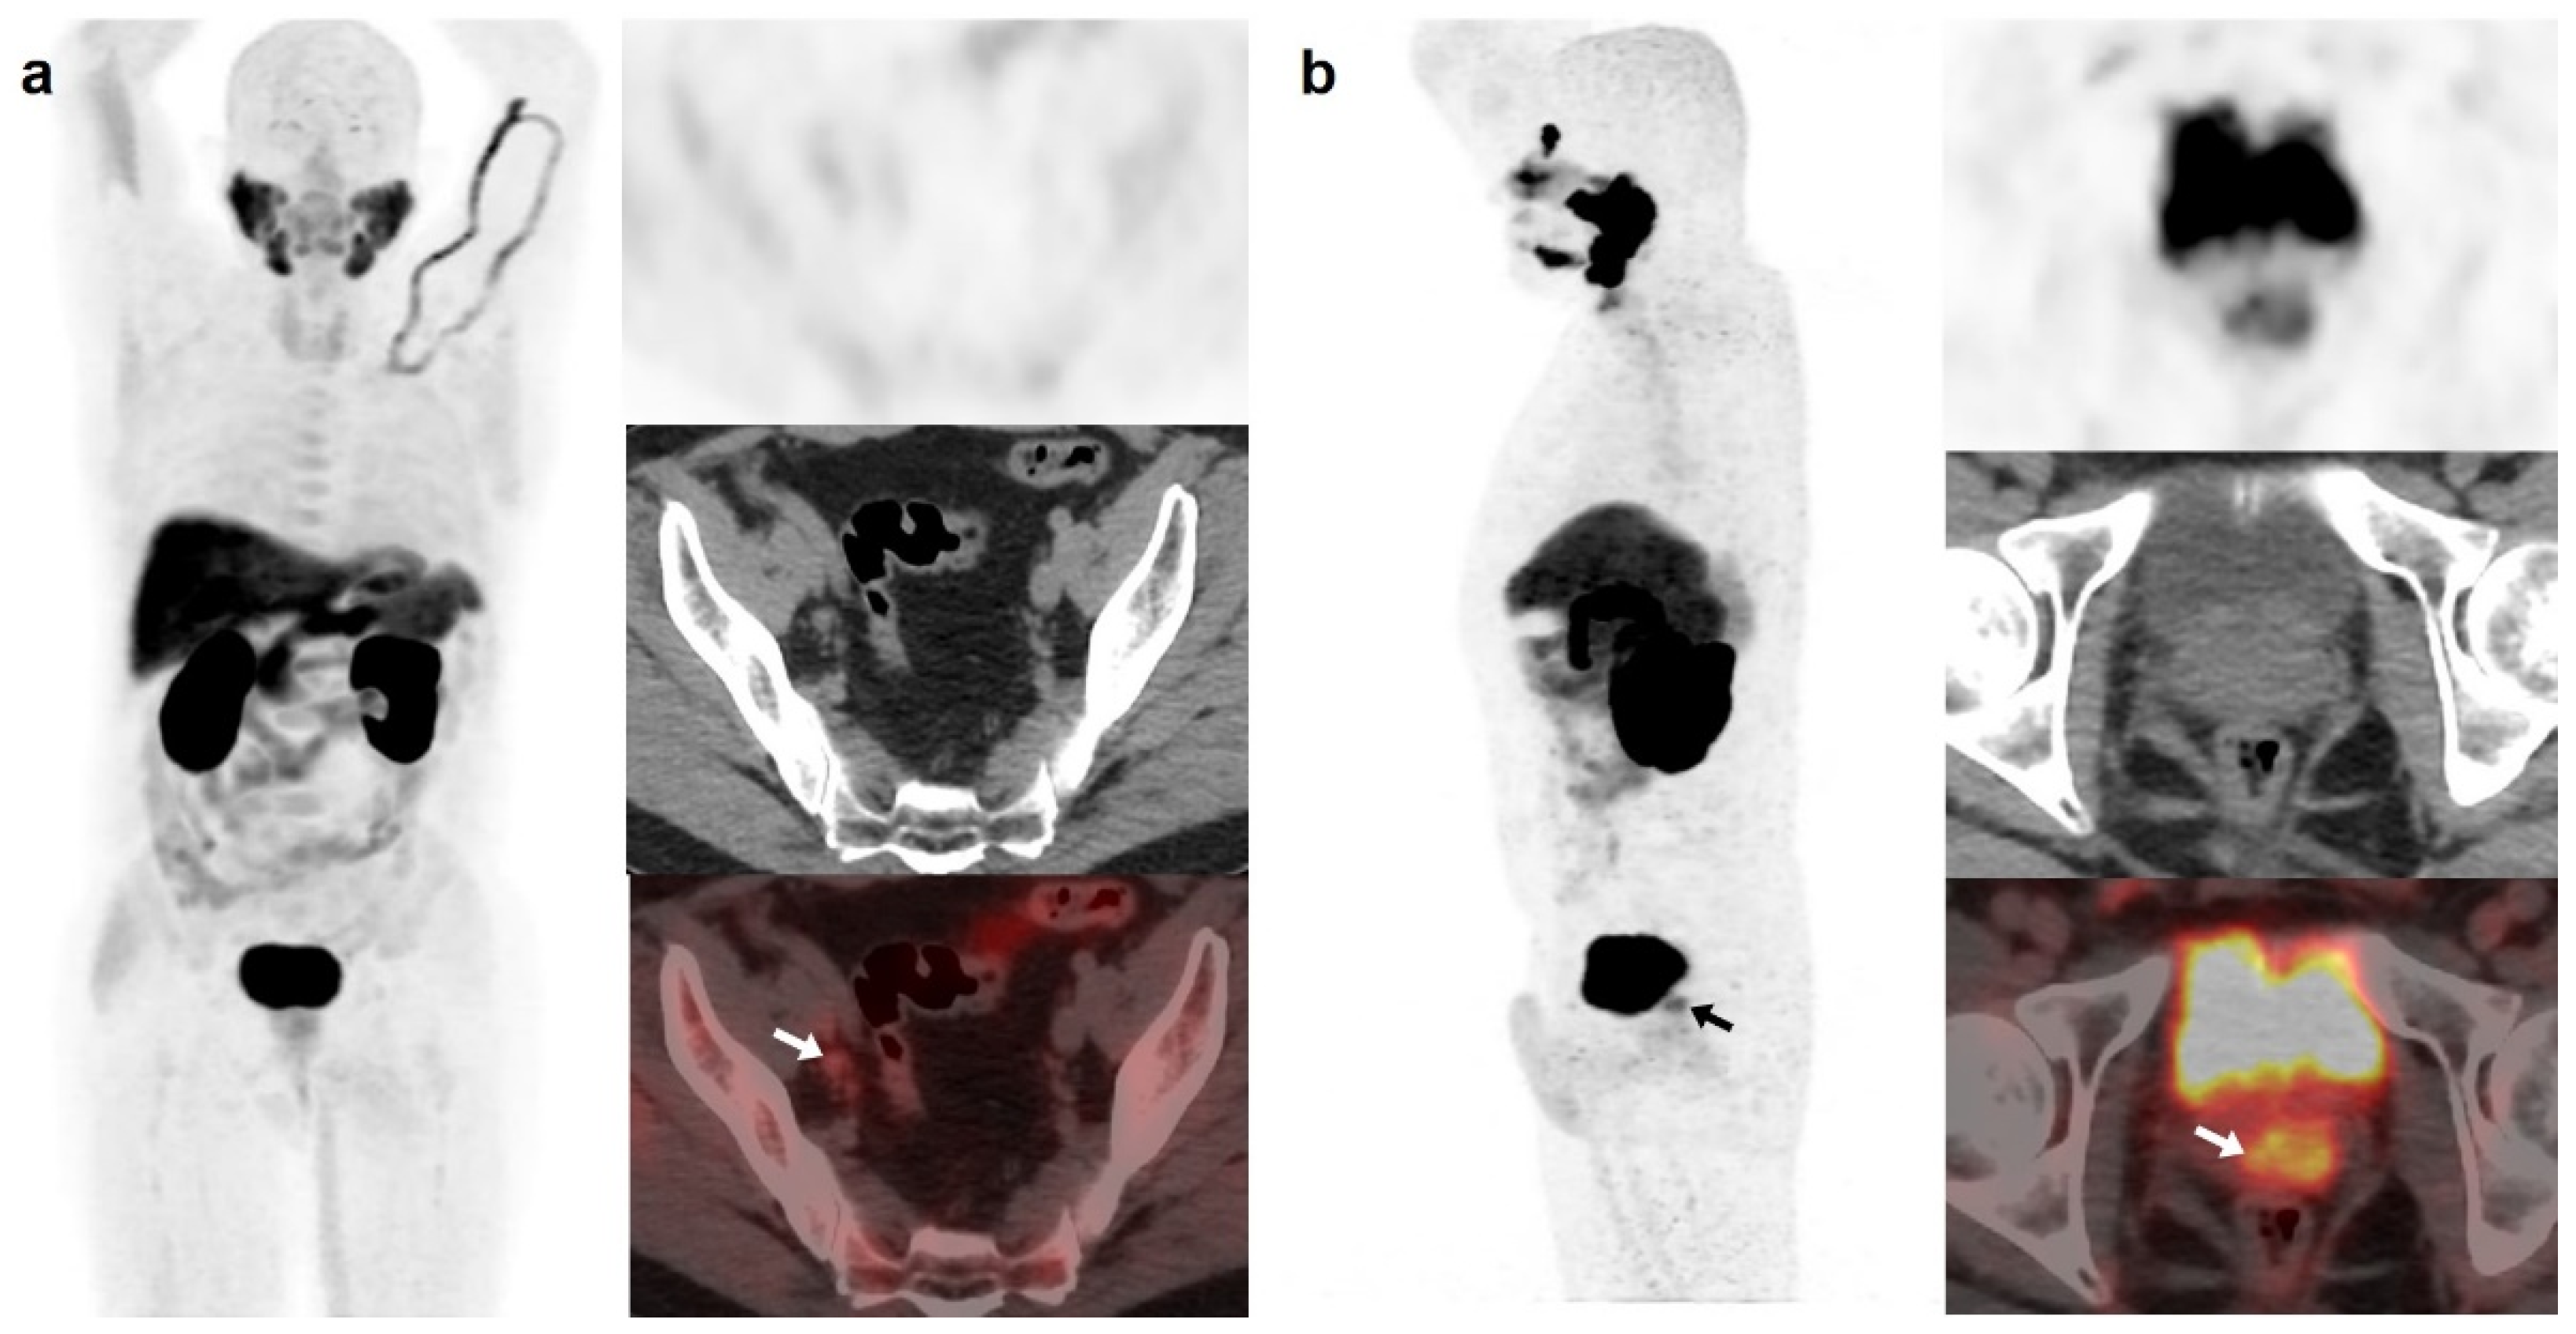

[18F]DCFPyL showed a higher DR than [18F]F-choline, 64.5% (89/138) and 33.3% (46/138), respectively. Both scans were negative in 44 patients (31.9%) and positive in 41 (29.7%). However, in 20/41 patients, [18F]DCFPyL visualized additional lesions compared with [18F]F-choline, which entailed miTNM stage change in 17 patients (Figure 1).

Figure 1.

59-year-old patient. Gleason 7 PCa treated with radiotherapy plus ADT. After ADT withdrawal BCR was detected (PSA 2.44 ng/mL, PSAdt 2.6 months, PSAvel 0.15 ng/mL/month). [18F]F-choline (a) demonstrated only prostatic uptake (white arrow) and [18F]DCFPyL-PET/CT (b) showed prostatic tracer uptake and lymph nodes metastases (white and black arrows). Time window of sixteen days between both scans. [18F]DCFPyL changed therapeutic management allowing escalation (ADT + Apalutamide).